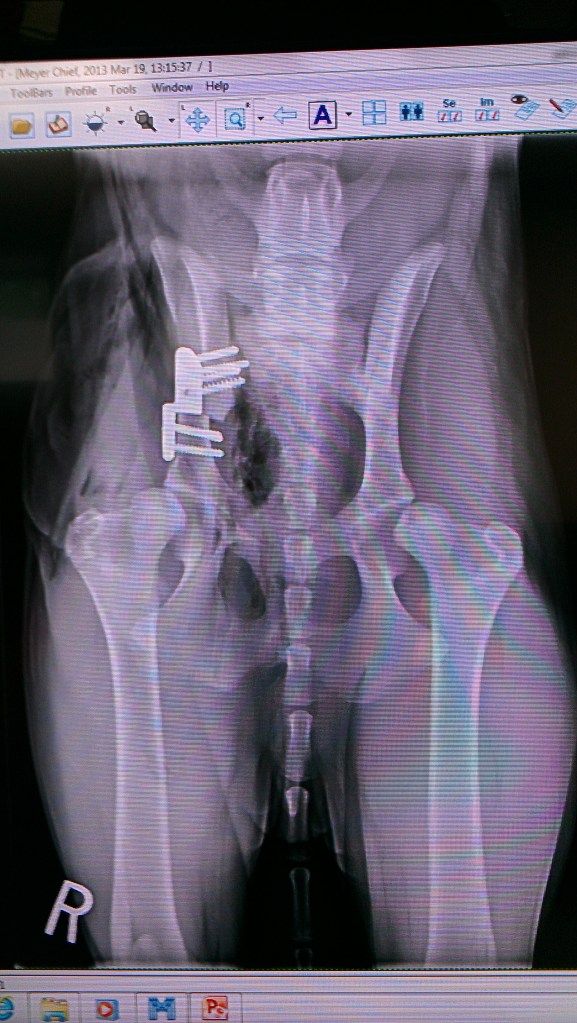

1st x-ray after surgery. You can see how the left hip is not really sitting in the socket…that’s how both hips were. As he healed, his right hip (surgical hip) was more in place.

Initially, the vet advised that we have his right hip done first, and then if we wanted to, to do the left one four weeks into recovery from the right leg. But the day of the surgery we learned that the left hip was displaced further than initially believed, and that it wasn’t guaranteed that they would be able to put it into socket enough for the surgery to work. The surgeon advised that we continue with the right leg, and then use other methods to control the left hip dysplasia when and if it ever bothered him. So that’s what we did, and I think it was the right decision, because they ended up having a harder time with his right hip than they thought they would, and they said that the left leg definitely wouldn’t have taken to the surgery. So in the end I’m glad we didn’t put him through all that for it to not be successful.